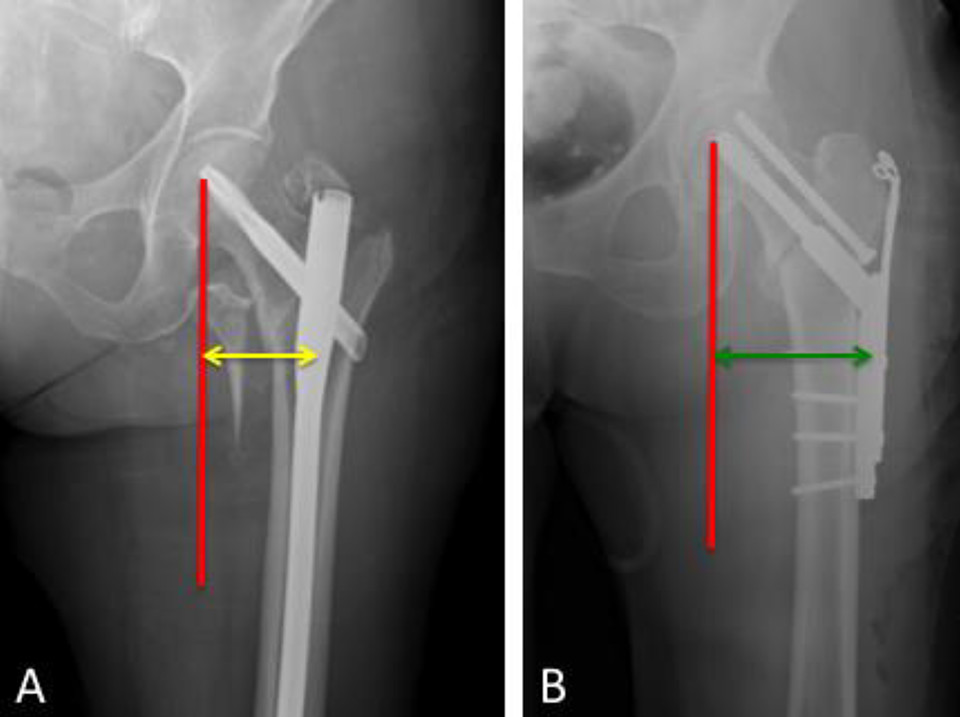

髓内固定比滑动髋关节螺钉提供更强的生物力学稳定性,尤其对于不稳定型骨折至关重要。缺乏接触的后内侧骨块会导致更大的内侧压力,转移至植入物。髓内固定装置能够更接近股骨头中心的力线,并且力臂较短,因此在相同作用力下,髓内钉的弯矩更小,能承受更大的破坏载荷(图11)。研究表明,使用髓内钉装置能显著减少骨折移位的风险,且其破坏载荷与滑动髋关节螺钉相当。前瞻性研究也表明,髓内固定术后不稳定型骨折的影像学结局较滑动髋关节螺钉更优,且骨不连的发生率更低。

图11. 示意图显示,与滑动髋螺钉(B)相比,髓内装置(A)更靠近通过股骨头中心的力矢量作用线,且力臂更短。因此,在相同作用力下,髓内钉承受的弯矩更小,能够抵抗更高的载荷直至失效。